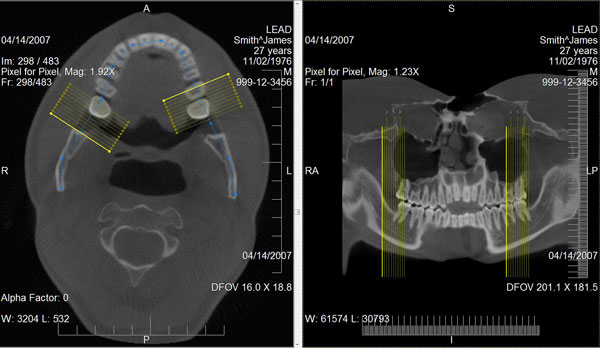

leadtools medical 3d sdk技术简化了二维医学影像切片三维医学可视化的重构技术,如mri和ct栈。leadtools medical 3d sdk技术提供了原始数据的许多不同的替代视图。它使用了三维重构技术如mpr、vrt、mip、minip和ssd,且支持裁剪平面、板、缩放、变焦、相机控制、阈值、透明度和影像处理的投影技术。

通过提供可视化的解剖细节,体数据的检查提高了解释、识别的速度和医师总测试评估的时间,这些仅仅利用二维切片是很难诊断的。

使用leadtools medical 3d sdk技术,开发者可创建使用任意二维横截面切片堆生成三维模型的应用程序。为了生成有意义的三维模型,横截面必须互相平行,因此leadtools提供了使用dicom标签识别、分离和设置体积栈的功能。

同时,leadtools medical 3d sdk提供了一个接口,可定义三维像素(体素)模型,还可通过三维模型的正确测量、方位标注和缩放进行患者定向,并生成斜交切片和正交切片。

leadtools medical 3d控件也能生成斜交和正交的二维mpr切片。通常情况下,一个mpr视图包括显示所需结构的三个正交平面视图和操纵这个体的方法。leadtools?medical 3d控件允许每个生成的二维正交平面(轴向、矢状和冠状)和独立的leadtools medical viewer 控件单元联系在一起。在这个配置中,leadtools?medical image viewer和leadtools medical 3d控件共同提供了交互式的三维光标同步和任意正交平面的支持。

通过使用先进的视角分析算法将弯曲的部分投影到一个平面上,曲面多平面重组可从一堆二维切片中生成二维的全景影像和近轴切影像。曲面多平面重组的使用在牙科和断层扫描(ct)专家中非常流行,他们需定期检查具有弯曲几何的骨骼,如牙齿和血管。

leadtools medical 3d sdk的裁剪平面功能允许用户生成一个切片,这个切片是通过虚拟裁剪一堆影像得到的。双切平面包含了两条互相垂直的切割线(横截面切割线)。这允许用户从各个方向观察一个物体的垂直切片,随后评估感兴趣的解剖。

开发者可编程设置切割线、切割线的旋转中心以及这个体堆中任意位置的切片厚度。除此之外,leadtools medical image viewer控件实现了交互式的单切割线和双切割线。使用leadtools medical image viewer控件,用户可以使用内置的操纵交互式的移动和旋转切割线,并选择切片厚度来查看一个厚的mip板。